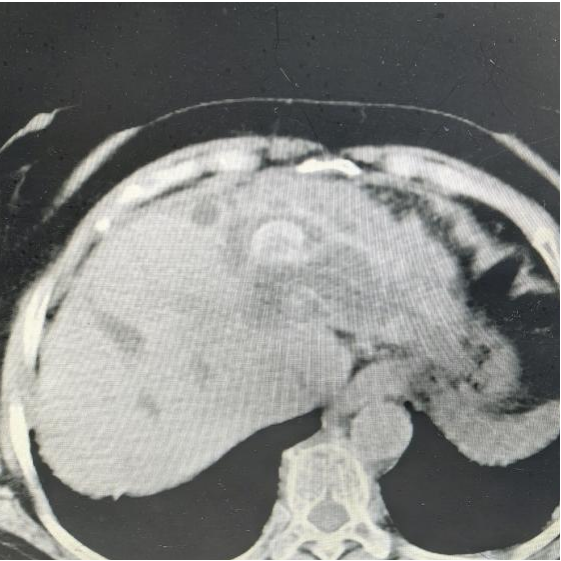

术前CT

送来医院一查,CT和磁共振片子上左肝内胆管和胆总管里密密麻麻全是结石,最大那颗跟核桃似的堵在那儿。肝内胆管结石、胆总管结石伴急性胆管炎、胆汁型肝硬化,老太太的皮肤和眼白都泛着黄。